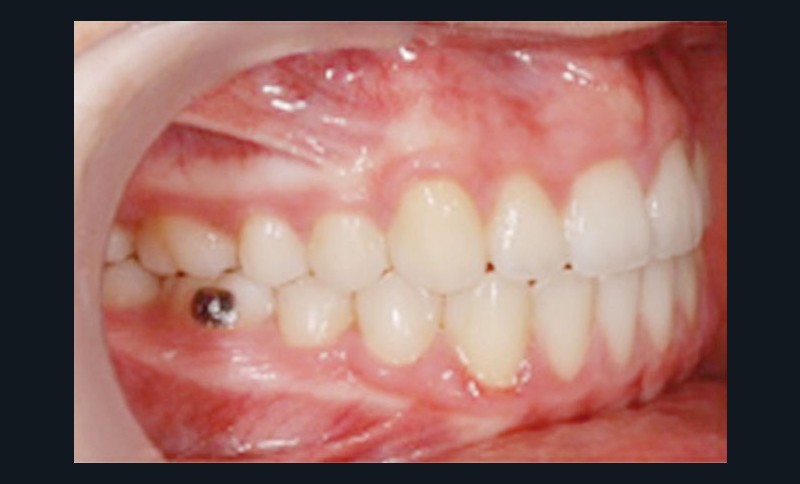

Sans aucun appareillage d’expansion, le maxillaire a été transformé et semble avoir été soumis à une disjonction (fig. 30).

Les moulages avant-après montrent une augmentation du sens transversal de 10 mm au niveau des 1re et 2e prémolaires (fig. 31).